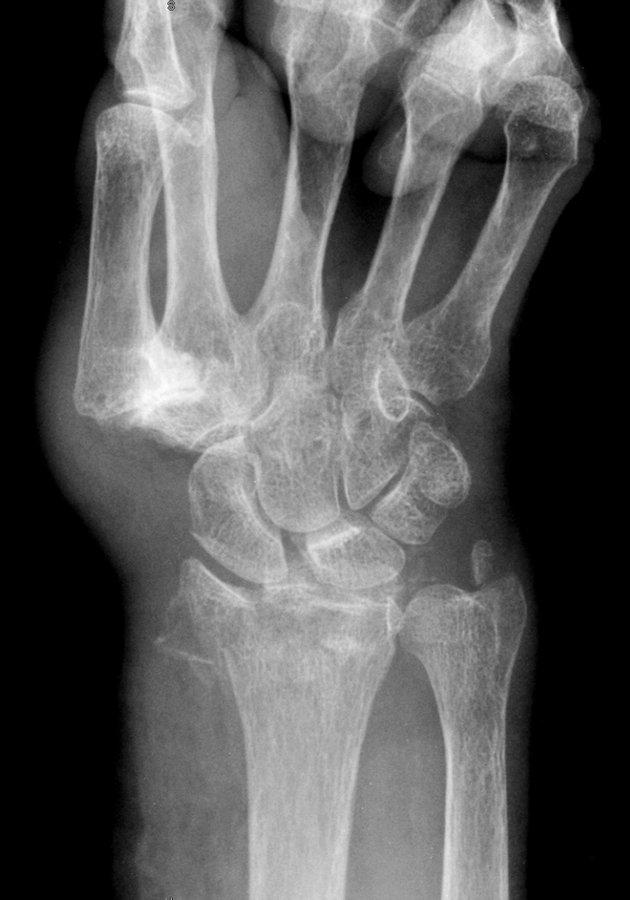

Ob traumatisch oder nicht: Ein Bruch ist ein Bruch. Ob traumatisch oder nicht: Ein Bruch ist ein Bruch. © Science Photo Library/Steven Needell

Colles-Fraktur des distalen Radius und Abrissfraktur des Processus styloideus ulnaris­ im Handgelenk einer 94-Jährigen. Colles-Fraktur des distalen Radius und Abrissfraktur des Processus styloideus ulnaris­ im Handgelenk einer 94-Jährigen. © Science Photo Library/Steven Needell